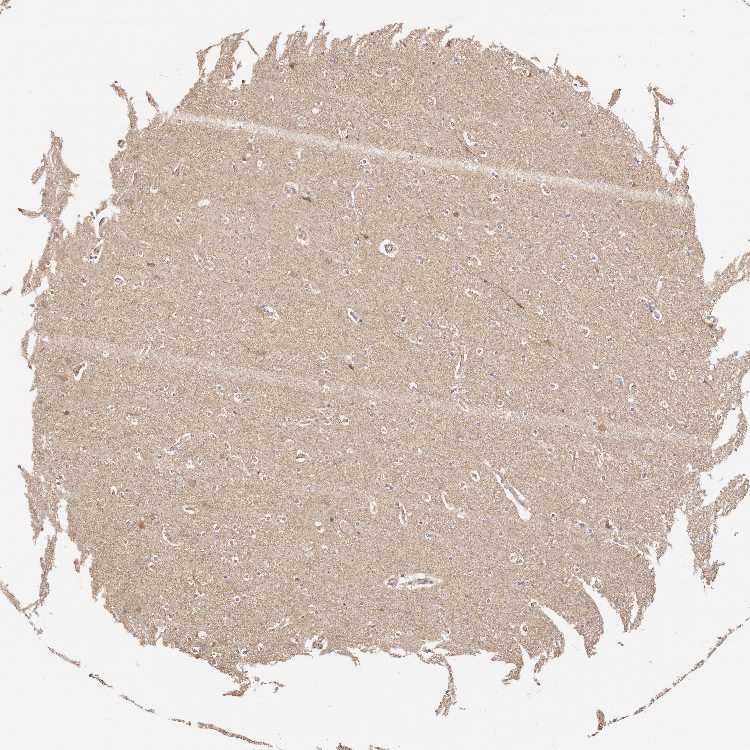

AFDN